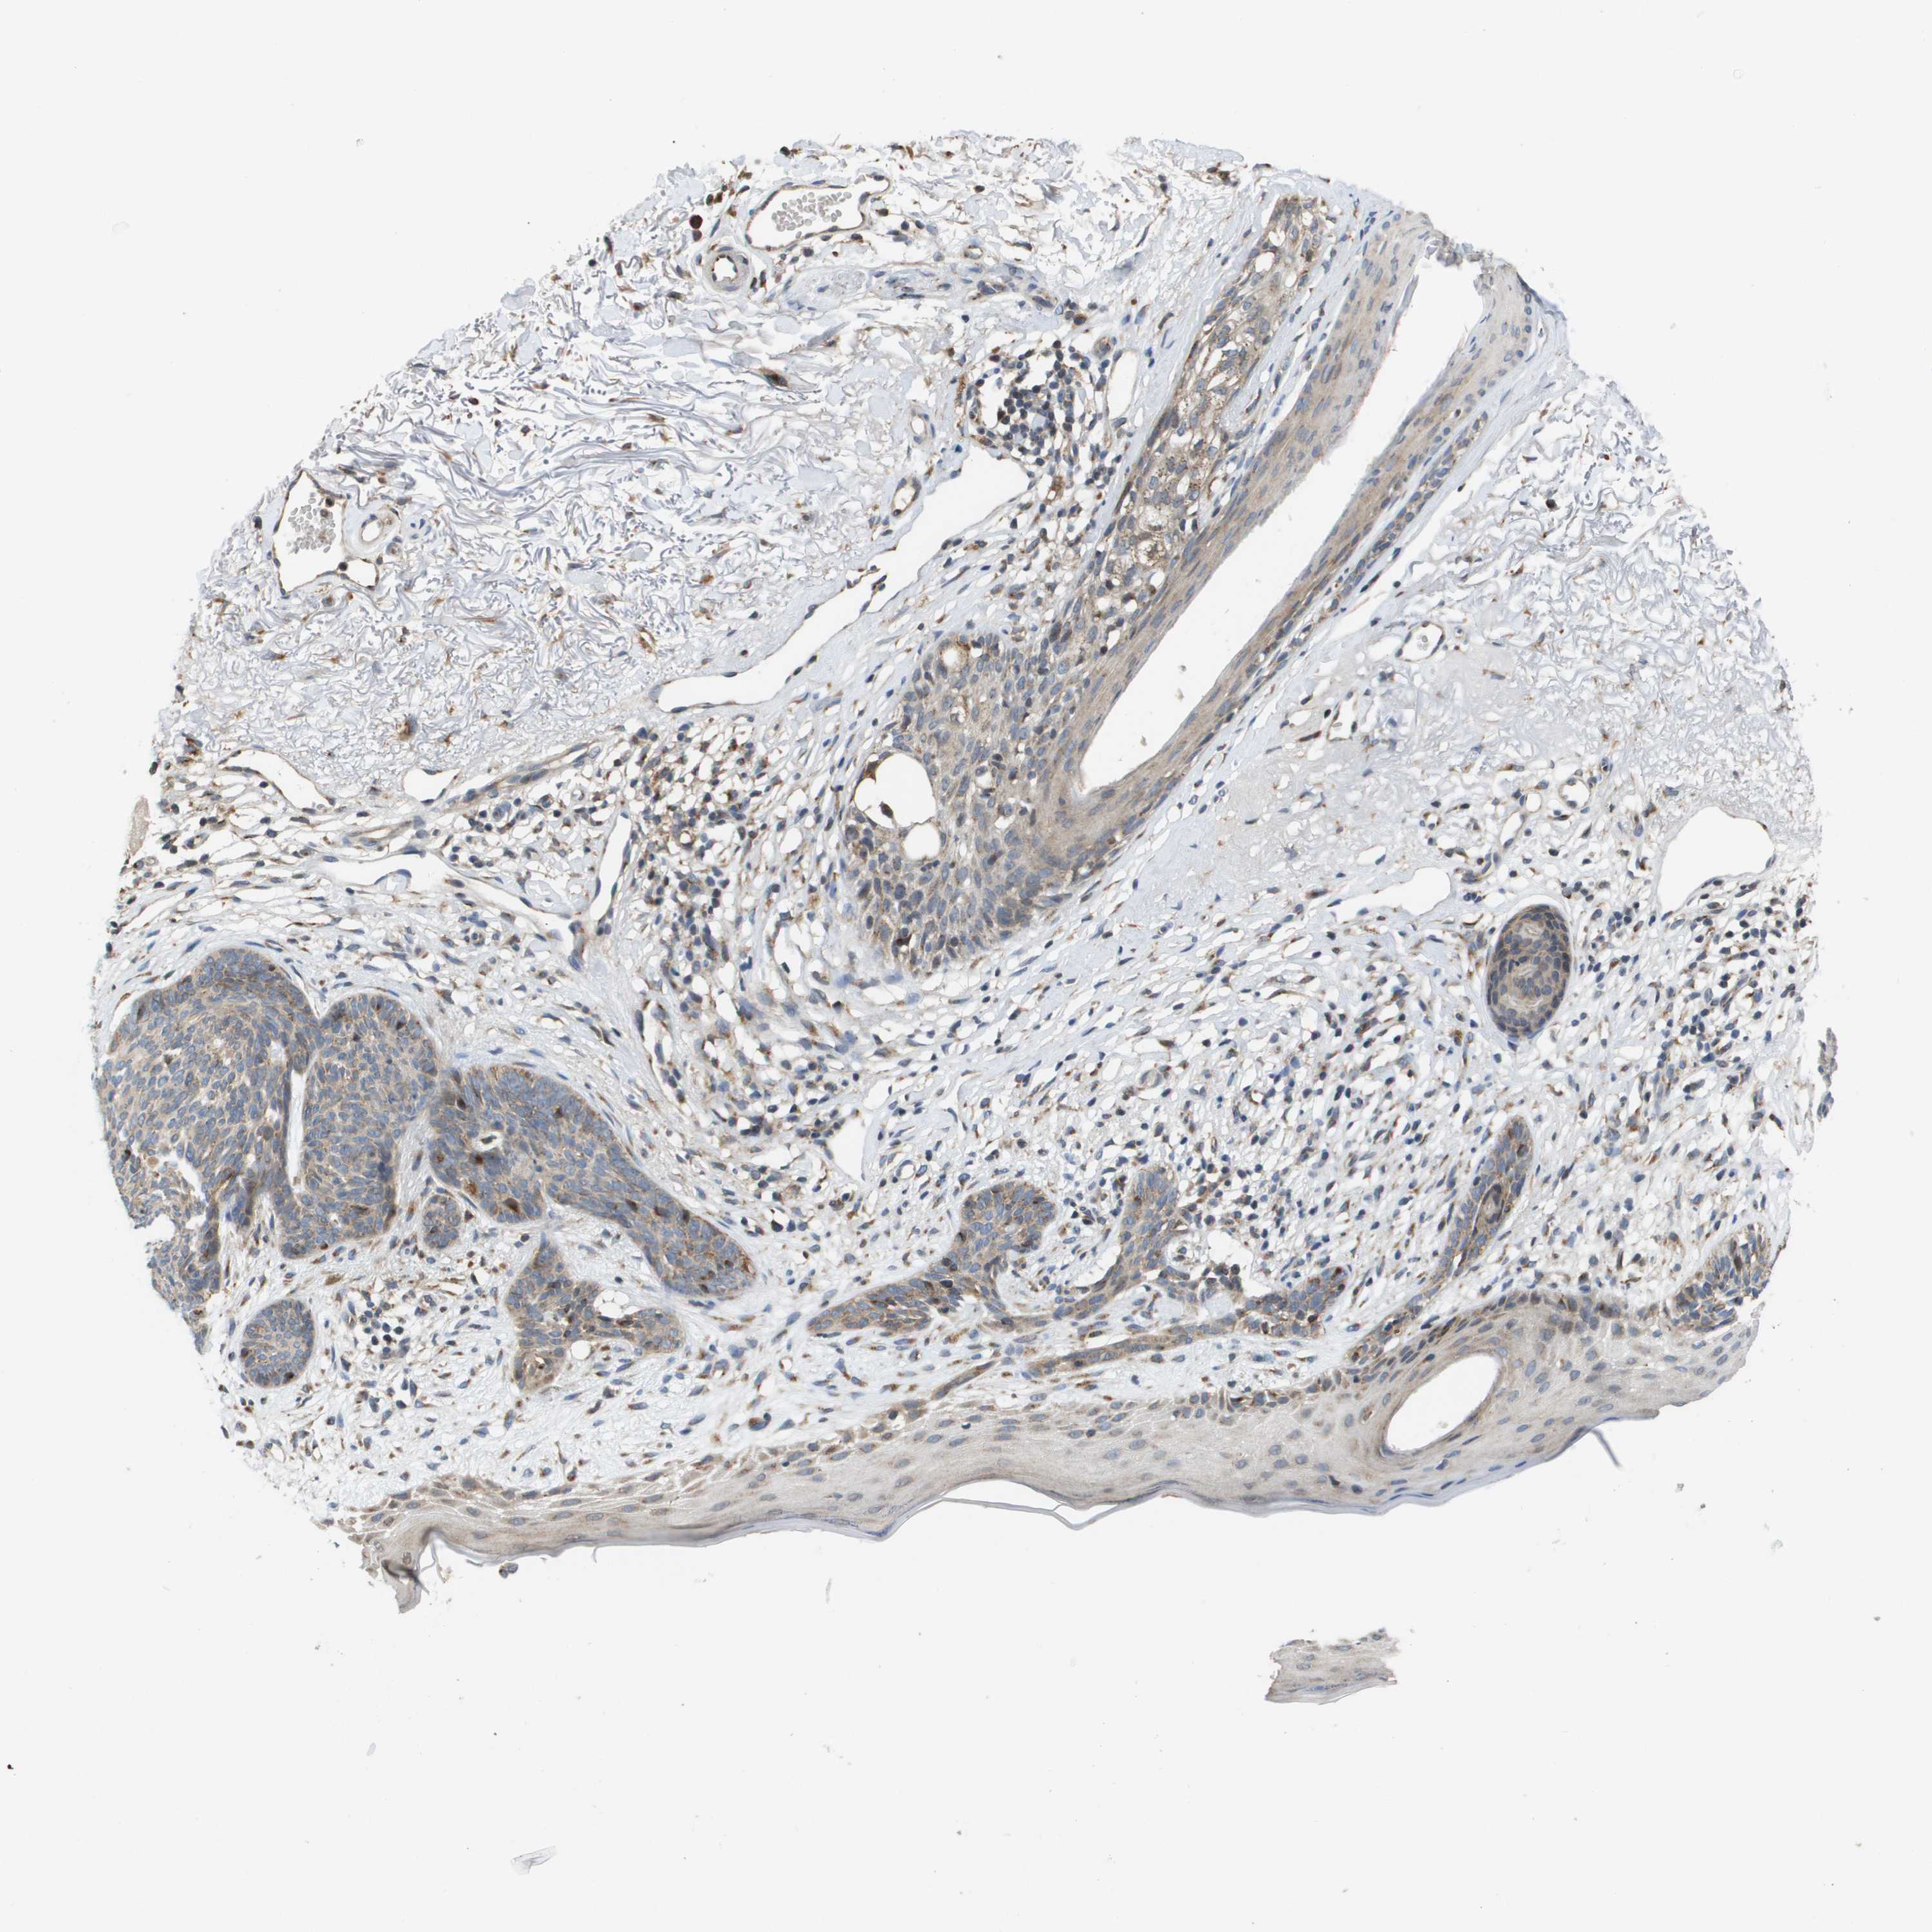

SKIN CANCER - Protein expressioni

A mouse-over function shows sample information and annotation data. Click on an image to view it in a full screen mode. Samples can be filtered based on level of antibody staining by selecting one or several of the following categories: high, medium, low and not detected. The assay and annotation is described here.

Each image is clickable and will lead to virtual microscopy that enables deeper exploration of all samples and also displays staining intensity scores, fraction scores and subcellular localization as well as patient and tissue information for each sample.

Antibody HPA006277

Antibody HPA006507

Antibody CAB017027

Staining

High

Medium

Low

Not detected

Intensity

Strong

Moderate

Weak

Negative

Quantity

>75%

75%-25%

<25%

None

Location

Nuclear

Cytoplasmic/membranous

Cytoplasmic/membranous,nuclear

Squamous cell carcinoma, NOS

Basal cell carcinoma

Squamous cell carcinoma, metastatic, NOS